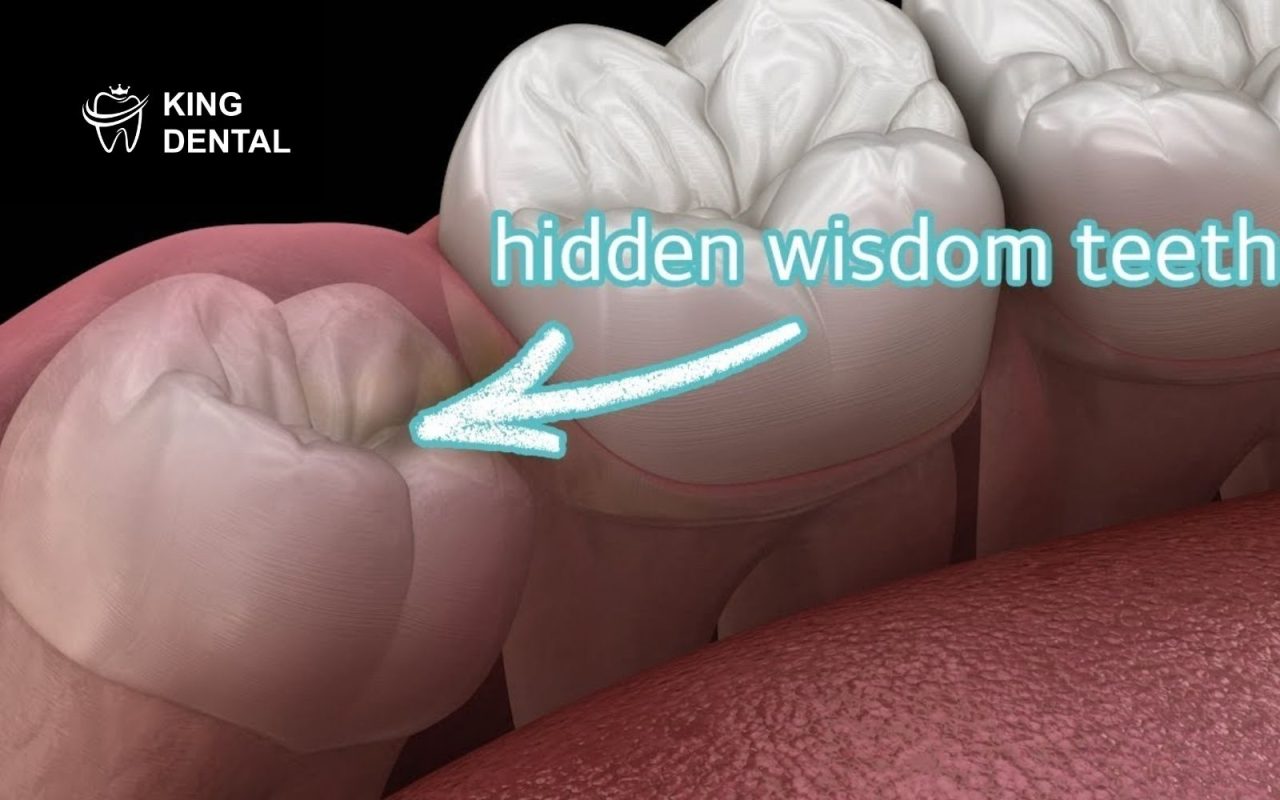

- Răng khôn mọc sai hướng

Răng có thể mọc xiên hoặc mọc ngang. Điều này gây chèn ép và viêm kéo dài.

- Tạo túi lợi trùm gây đau dai dẳng

Lợi trùm che phủ răng khôn. Khi thức ăn mắc vào, khu vực này dễ bị viêm.